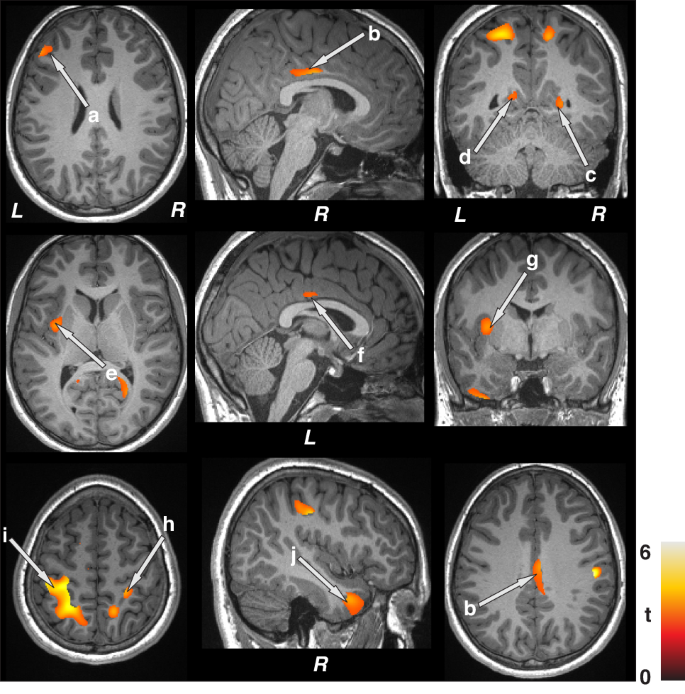

Whole-brain GM volume maps were correlated voxel-by-voxel with focal seizure frequency index (number of seizures per day) in epilepsy patients using partial correlations (SPM12; covariates, age, sex, and BMI, uncorrected, p < 0.005, minimum extended cluster size, 40 voxels) (Fig. 3). Brain clusters showing significant correlations between gray matter volumes and focal seizure frequency indices were overlaid onto background images for structural identification. Additionally, partial correlations were performed with covariates, age, sex, BMI, symptomatic epilepsy, nocturnal seizures, and neurodevelopmental disabilities (SPM12; uncorrected, p < 0.005, minimum extended cluster size, 40 voxels) (Supplementary Fig. 3).

Positive correlations emerged between gray matter volumes and focal seizure frequency indices in children with epilepsy in the frontal cortices (a), bilateral mid (b, f) and posterior (c, d) cingulate, left insula (e), putamen (g), bilateral parietal cortices (h, i), and temporal cortices (j). Figure conventions are the same as in Fig. 1.

Associations between gray matter volumes and focal seizure frequency indices

Focal seizure frequency indices showed positive correlations with regional gray matter volumes in multiple areas (Fig. 3) using whole-brain voxel-by-voxel partial correlation procedures. These regions included the frontal cortices (a), bilateral mid (b, f) and posterior (c, d) cingulate, left insula (e), putamen (g), bilateral parietal cortices (h, i), and temporal cortices (j) in those children at high risk for SUDEP. The correlation coefficients demonstrating the strength of the associations between gray matter volume abnormalities and focal seizure frequency indices are shown in Table 2. These regions survived significance levels even after adding additional covariates, such as symptomatic epilepsy, nocturnal seizures, and neurodevelopmental disabilities (Supplementary Fig. 3).